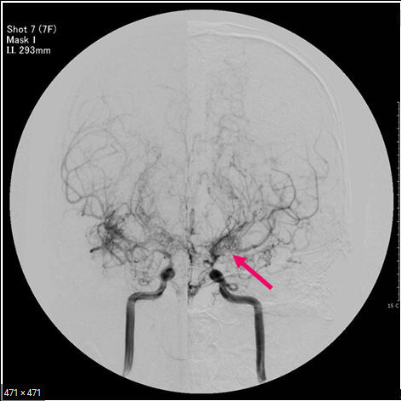

모야모야병은 특별한 이유가 없이 전대 뇌동맥과 중대 뇌동맥 시작 부분에 협착 또는 폐색이 보이고 해당 부근에 모야모야 혈관이라는 작은 이상 혈관이 발견되는 것을 말합니다.

양쪽 내경동맥이 모두 좁아지는것이 정의에 해당되지만 약 10% 환자들이 한쪽 내경동맥만 좁아지는 일명 일축성 모야모야병을 보여준다고 알려져 있습니다.